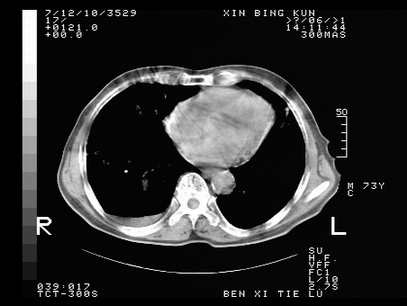

标题: CT10820:男,73岁,病史肺TB,现病史肺炎,直肠CA术后 [打印本页]

标题: CT10820:男,73岁,病史肺TB,现病史肺炎,直肠CA术后

双肺间质改变,依据病史双肺多发结节灶考虑转移,少量胸水.

1.两肺结核.2.两肺多发转移瘤.3右侧少量胸腔积液4.主动脉钙化.

双肺多发结节及条片状致密影,右侧少量胸腔积液。临床:直肠ca术后,肺tb病史。综合考虑:1 双肺转移!2 继发性肺结核合并感染!

此人病史较复杂,原有肺结核,直肠癌术后。肺部病灶形态亦呈多形性。因此,不可仅以一种病来解释肺部的病变。双肺多发的类圆形结节灶,结合病史还是首先考虑转移瘤,而双肺其余病灶还需结合化验室检查,结核或肺部感染在无其它检查资料的情况下不好排除。还是那句话----放射科医生不是开照像馆的,我们也是医生,看片一定要多结合临床及其它检查资料。要当一名合格的放射科医生,并不比当一名临床医生容易,我们可别把自已不当医生看。

两肺多发结节影,并见滋养动脉与其相连,考虑 两肺转移. 右侧胸腔积液考虑胸膜转移.

左肺上叶下叶背段,右肺中下叶见多发斑片状、条索状高密度影,兵变周围小结节影形成“树芽”样改变。 左肺上叶舌段近前胸壁处及右肺中叶内侧段见结节影。右侧胸膜腔内见液体密度区。纵隔内未见明确增大淋巴结。考虑左肺上叶舌段近前胸壁处及右肺中叶转移瘤可能性大。两肺继发型肺结核。右侧胸腔积液。

还有心包少量积液。